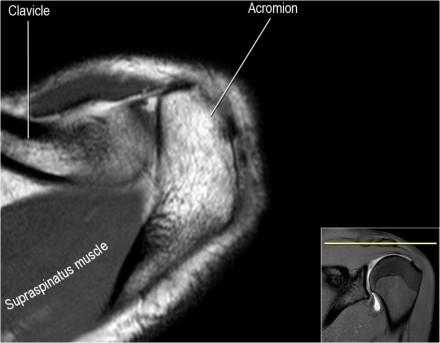

Нормальная корональная анатомия плечевого сустава и контрольный список

- обратите внимание на клюво-ключичную связку (coracoclavicular ligament) и короткую головку двуглавой мышцы (short head of the biceps).

- обратите внимание на клювоакромиальную связку (coracoacromial ligament).

Нормальная сагиттальная анатомия и контрольный список

- обратите внимание на мышцы манжеты вращателей и поищите их атрофию